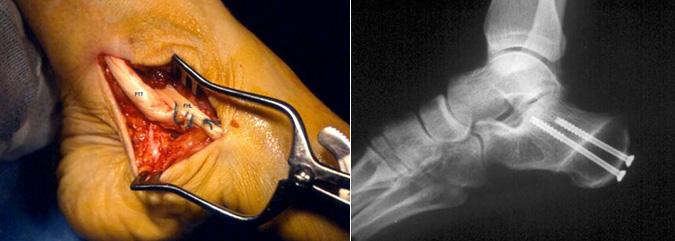

- Fraturas: Podem ser tratadas com redução aberta e fixação interna (RAFI), tração esquelética ou fixação externa.

- Luxações: Geralmente corrigidas com RAFI ou tração esquelética.

- Artrite: Tratada com artroplastia (substituição articular), artrodese (fusão articular) ou osteotomia (corte ósseo para realinhamento).

- Deformidades do pé (ex: pé plano ou cavo): Corrigidas com osteotomia, artrodese ou transferência de tendões.